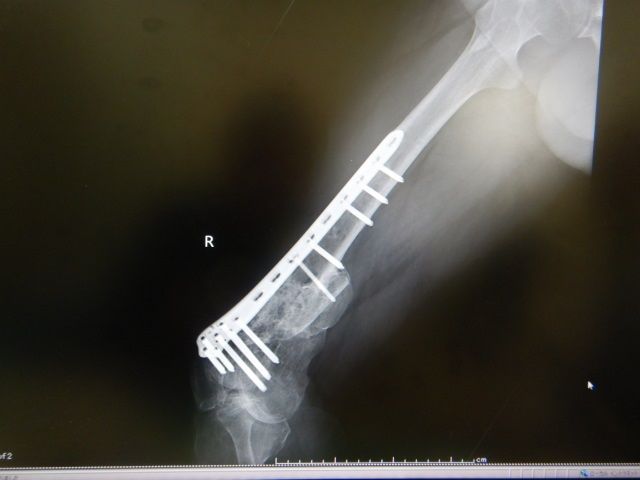

±¦ÂȾǯÄê´üÅÀ¸¡

¼õ½ý¤«¤éº£Ç¯¤Ç13ǯÌܤȤʤꡢȾǯËè¤ÎÄê´ü¸¡ºº¤Ë¹Ô¤Ã¤Æ¤¤Þ¤·¤¿¡£

ÆÃ¤Ë²Ä¤â̵¤¯ÉԲĤâ̵¤¯ÊѲ½¤âº¹¤Û¤É¸«¤é¤ì¤Ê¤¤¾õÂ֤Ǥ¹¡£

°ì±þÈô¹Ôµ¡¤Ë¾è¤ë¤«¤âÃΤì¤Ê¤¤¤È»×¤¤

ÆüËܸì¤È¸øÍѸì¤Î±Ñ¸ì¤Ç¿ÇÃǽñ¤ò

½ñ¤¤¤ÆÌ㤤¤Þ¤·¤¿¤¬º£¤Î½ê³¤³°½ÐÄ¥¤Ï̵¤¤¤«¤âÃΤì¤Ê¤¤¡£

¥í¥Ã¥¥ó¥°¥×¥ì¡¼¥È¤ò³°¤·¤¿¤¤¤±¤É

¤Þ¤À¡¢¤Þ¤¿ÀÞ¤ì¤ë¥ê¥¹¥¯¤¬¤¢¤ë¤Î¤Ç

¤³¤Î¥Á¥¿¥ó¥×¥ì¡¼¥È¤Ï¡¢¾Æ¾ì¤Þ¤Ç»ý¤Ã¤Æ¤æ¤¯»ö¤Ë¤Ê¤ê¤½¤¦¡£